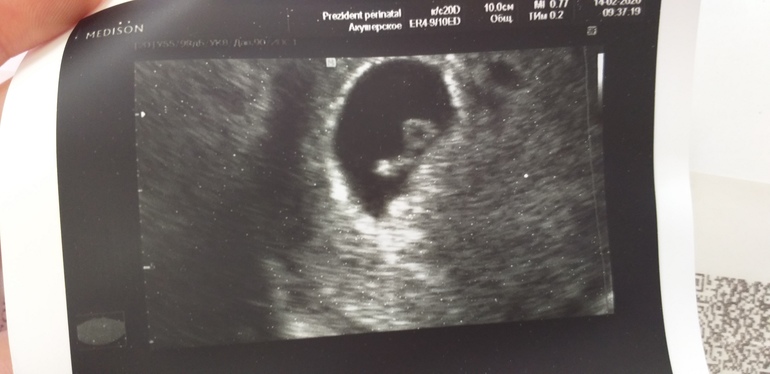

Но всё оказалось хорошо! Малыш подрос, чсс 148, ктр 4,5мм (4 дня назад был 3,1). Гематом и отслоек не нашли, смотрели долго и тщательно. Сказали гипертонус по задней стенке, возможно поэтому болит поясница. Сосуды "рыхлые", возможно "что-то" было, но сейчас нет (я так поняла "что-то" - на пример гематома). Мазня не красная- хорошо. Коричневая- значит выходит старая кровь ...

Сделали фото 🥰